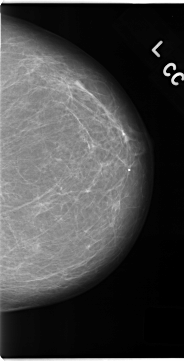

C_0155_1.LEFT_CC

LEFT_CC LINES 4688 PIXELS_PER_LINE 2392 BITS_PER_PIXEL 12 RESOLUTION 50 NON_OVERLAY